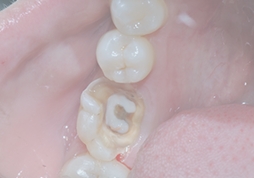

這些問題引起的牙疼要杜牙根~

深齲

蛀牙